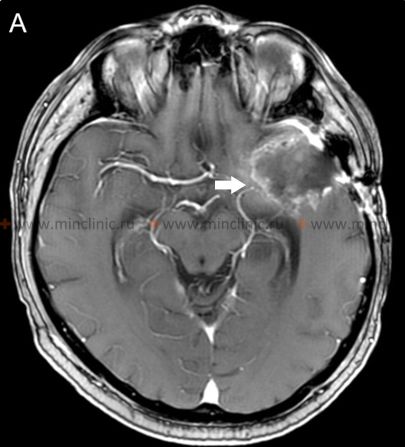

გადამწყვეტია, სანამ დაიწყება ანტიკოაგულანტური თერაპია (სისხლის გამათხელებლები) პაციენტში, რომელსაც აქვს მწვავე ინსულტის სიმპტომები, რომლებიც მიუთითებს ცერებრულ ემბოლიაზე, აუცილებელია ჩატარდეს თავის ტვინის გადაუდებელი ვიზუალიზაცია, როგორც წესი, უკონტრასტო კომპიუტერული ტომოგრაფია (კტ)[16]. ამ საწყისი სკანირების მთავარი მიზანია ინტრაკრანიალური სისხლჩაქცევის (ჰემორაგიის) საიმედოდ გამორიცხვა, რადგან ანტიკოაგულანტები უკუნაჩვენებია ჰემორაგიული ინსულტის დროს და შეიძლება გააუარესოს სისხლდენა [16]. მიუხედავად იმისა, რომ კტ შესანიშნავია მწვავე სისხლის აღმოსაჩენად, მაგნიტურ-რეზონანსული ტომოგრაფია (მრტ) უფრო მგრძნობიარეა ადრეული იშემიური ცვლილებების აღმოსაჩენად და მწვავე და ქრონიკული სისხლჩაქცევების ან წინა ინფარქტების ერთმანეთისგან გასარჩევად [14, 16].

თუ ეჭვია ცერებრული არტერიის ემბოლიაზე, არტერიული ოკლუზიის ადგილმდებარეობის იდენტიფიცირება და ქვემოთმდებარე ტვინის ქსოვილის შეფასება კრიტიკულია მწვავე მკურნალობის (როგორიცაა თრომბექტომია) დასაგეგმად [16, 19]. არაინვაზიური სისხლძარღვოვანი ვიზუალიზაცია, როგორიცაა კტ ანგიოგრაფია (CTA) ან მრ ანგიოგრაფია (MRA), ჩვეულებრივ ტარდება გადაუდებლად [16]. კონვენციური კათეტერზე დაფუძნებული ცერებრული ანგიოგრაფია (ციფრული სუბტრაქციული ანგიოგრაფია - DSA) უზრუნველყოფს სისხლძარღვების უმაღლესი რეზოლუციის დეტალებს, მაგრამ არის ინვაზიური [14]. ის შეიძლება ჩატარდეს, თუ იგეგმება ენდოვასკულური მკურნალობა (თრომბექტომია) ან თუ არაინვაზიური ვიზუალიზაცია არასაკმარისად ინფორმატიულია [16, 19]. მნიშვნელოვანია აღინიშნოს, რომ რამდენიმე საათის ან დღის შემდეგ, ემბოლმა შეიძლება მიგრირება განიცადოს დისტალურად, ფრაგმენტაცია ან სპონტანური ლიზისი (დაშლა), რაც ნიშნავს, რომ მოგვიანებით ჩატარებულმა ანგიოგრაფიამ შეიძლება არ აჩვენოს თავდაპირველი ოკლუზია, რის გამოც ემბოლიური ინსულტის საბოლოო დიაგნოზი ზოგჯერ სავარაუდოა კლინიკური სურათისა და ინფარქტის პატერნის საფუძველზე [1]. სტანდარტული ინტრავენური კონტრასტის შეყვანა რუტინული კტ ან მრტ სკანირების დროს ზოგადად მოკლებულია იმ რეზოლუციას და დროით სიზუსტეს, რაც აუცილებელია სისხლძარღვებში მცირე ცერებრული ემბოლების უშუალო ვიზუალიზაციისთვის [14].